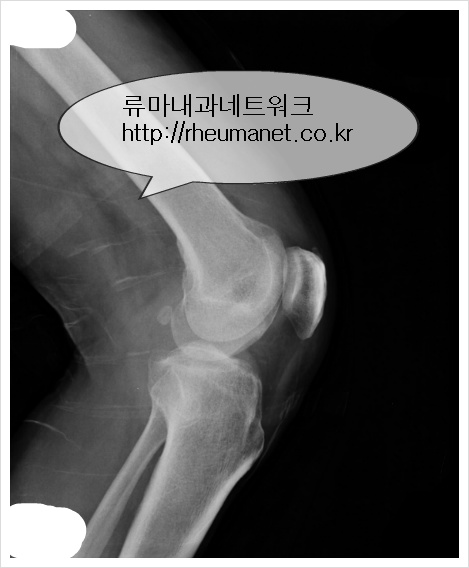

↑'무릎이 아파요' 류마티스관절염 환자 x-ray사진

류마티스관절염의 증상중에도 무릎이 아파요,무릎이 저려요 등 무릎통증과

손가락 마디가 아파요,자고 일어나면 손이나 발이 뻣뻣해요 등의 관절통증이

오는 경우가 있습니다.